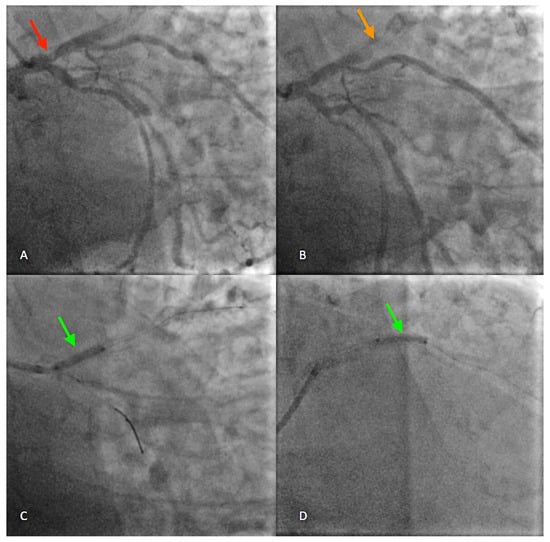

Figure 2. Approximately three weeks later, the patient returned to the emergency department complaining of fever, anterior chest pain, dyspnea at rest, and high BP values at home. ECG findings were similar to the previous exam. Laboratory analyses again showed increased values of troponin T (256.4 pg/mL), C-reactive protein (8 mg/dL), and NT-proBNP (11,594 Pg/mL). Peripheral blood cultures and pericardial fluid analysis were performed, and the culture media developed colonies of facultatively anaerobic Staphylococcus aureus, resistant to methicillin. A contrast-enhanced chest computed tomography (CT, GE Revolution 256 × 2) examination was ordered which did not detect acute lung lesions. However, complete separation of the proximal LAD stent into two fragments, with a distance of ~5 mm in between, was observed ((A), red arrow). A pericardial hematoma around the trunk of the pulmonary artery ((B), yellow arrows) and a saccular enlargement with transverse diameters of ~10/12 mm between the two stent fragments were identified ((C,D), red arrows). Therefore, the CT diagnosis was a fracture of the distal segment of the proximal LAD stent associated with pseudoaneurysm of the anterior descending artery and pericardial hematoma. Stent fracture can occur due to various causes including heavy calcification, left ventricle remodeling, stent length and overlap, arterial flexion, implant duration, and material fatigue; ongoing efforts aim to increase lifespans by improving flexibility and tear resistance [1,2,3].